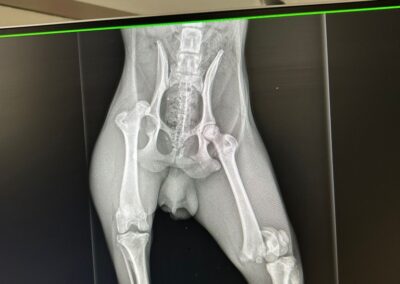

Il souffre d’une fracture du fémur et d’une luxation sur l’autre patte .